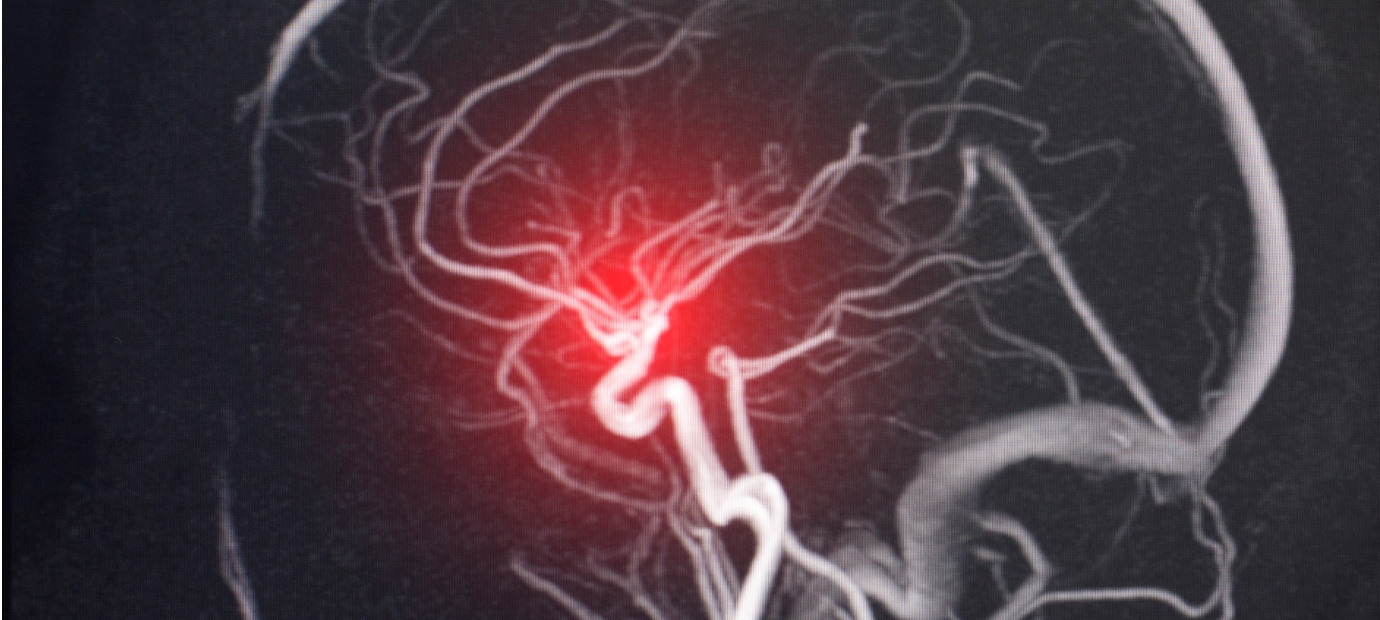

MRA検査 Magnetic Resonance Angiography

おもに、くも膜下出血の原因となる脳動脈瘤発見など、脳血管障害の発見に用いられます。脳血管のみを立体的に抽出する検査で、血管の様子がわかる立体画像を表示することが可能です。血管の狭窄や、梗塞による血流異常、脳動脈瘤の有無などを診断します。